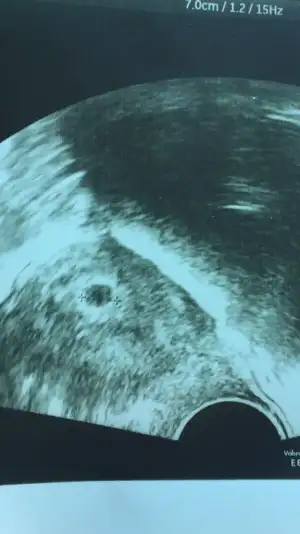

Erken gebelik testi yapsaydın olup olmadığı daha net belli olurdu. Kaset testlerde çizgi erken belli olmuyor. Birazda odaklanmamış kamera o bölgeye dolayısıyla ben göremedim çizgi. İnş vardır.Merhaba kızlar burda herkes gebe,sanırım sizede danışayım. Bugun transferın 8. Günü 5.gn embryosu konuldu. Testin bı sekildeamz çok silik biliyorum umarım birşey vardırEki Görüntüle 3126802